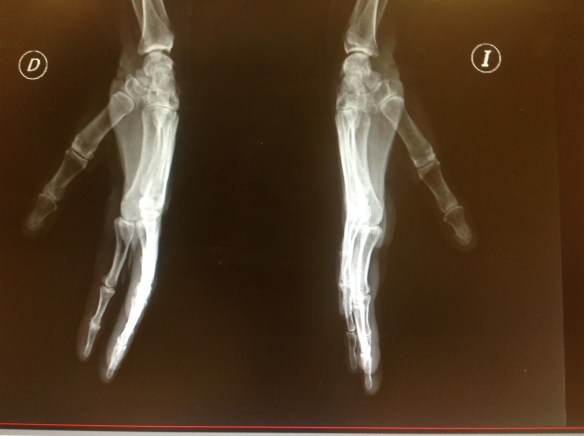

Para valorar realmente una anteroposterior de la columna de pulgar , debe solicitarse que sobre el book radiológico el paciente coloque la cara dorsal del pulgar manteniendo la mano pronada y la primera comisura bien abierta para evitar que los dedos trifalángicos se sobrepongan al pulgar. Si realizamos una anteroposterior de la columna del pulgar sin apoyar el de do sobre el book, la inclinación que adoptará el dedo no nos permitirá ver bien las articulaciones.

Estas 2 proyecciones, bien realizadas, nos permitirán valorar las articulaciones interfalángica, metacarpofalángica, trapeciometacarpiana, escafotrapeciotrapezoidea con un ángulo de 90 grados entre cada proyección .

Podremos así diagnosticar subluxaciones, luxaciones, pinzamientos articulares ,…